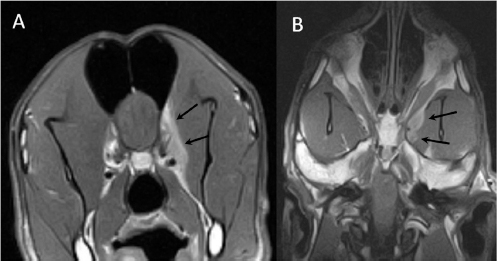

A 3-year-old female Great Dane was referred for acute onset behavioral changes (aggression and disorientation) of 2 weeks duration, and seizures from 24 hours prior to presentation. Physical examination revealed no abnormalities in body temperature, body condition score, heart rate, pulse quality, or cardiopulmonary auscultation. All lymph nodes were considered of normal size and no pain was elicited upon manipulation of the orbital, aural, or cranial musculature. Neither was there any history of dermatological or traumatic lesions in the eye, ear, or mouth. The neurological examination revealed the patient to be obtunded with decreased postural reactions and menace response worse in the left side. Neuroanatomic lesion localization was considered focal in the right prosencephalon with a possible increase in intracranial pressure. Hematological and serum biochemical analysis showed no abnormalities. Magnetic resonance imaging was performed using a low-field magnet (Airis Mate; Hitachi, Tokio, Japan). The study revealed a left-sided single frontal intra-axial lesion affecting gray and white matter adjacent to the internal capsule at the level of the optic canal (Fig. 1). The lesion presented signal homogeneity characterized by hyperintensity on T2W and FLAIR sequences and hypointensity in T1W sequences with peripheral enhancement after intravenous contrast administration (Fig. 1A and 1B). The lesion had a round shape with the greatest diameter of 2.84 cm. This enhancement was also recognized in the surrounding meninges following the brain surface following sulci. A small linear tract observed was directed dorsally from the lesion through the corona radiata (Fig. 1B). The lesion was associated with extensive perilesional vasogenic edema that worsened the mass effect characterized by a midline shift. The orbital and medial pterygoid muscles also showed an intense enhancement (Fig. 2). The wing of the presphenoid bone was thinner than the contralateral bone (Fig. 1B). A CT scan (Astelion 16, Toshiba, Tokio, Japan) was performed after MRI that allowed the identification of osteolysis in the presphenoid bone immediately dorsal to the orbital fissure (Fig. 1C). CT scan also revealed a hypoattenuating intra-axial lesion located in the left frontoparietal lobe together with diffuse hypoattenuation of tissues adjacent to the left optic nerve and the left pterygoid muscle. Finally, CSF analysis showed no abnormalities. On the basis of advanced radiological findings, the main differential diagnosis was an intracranial abscess due to the extension of the extracranial septic process through presphenoid bone. Because of rapid neurologic deterioration and suspected increased intracranial pressure, surgical excision was planned. A modified left rostrotentorial craniectomy was performed. Temporalis muscle and fascia were retracted, extending the incision cranially through the temporal line. Once the frontal and presphenoid bones were exposed an area of osteolysis was observed in the wing of the presphenoid bone immediately dorsal to the orbital fissure. The craniectomy (approximately 3 cm diameter) was centered on the osseous defect. A mucopurulent discharge presented immediately after the incision of the dura mater. A sample was collected for its microbiological study. The surgical site was flushed with sterile saline revealing the tip of a grass awn which was extracted from the brain parenchyma together with a small amount of purulent fluid (Fig. 3). After extensive flushing, the meninges were left open to allow drainage and the incision was closed as per routinely. Postoperative CT showed the correct location of the craniectomy and resolution of the abscess which was substituted by gaseous content but remained inside and on the dorsal surface of the frontal lobe (Fig. 4). Immediate postoperative therapy consisted of amoxicillin + clavulanic acid (Synulox 500, Zoetis Spain SL) 22 mg/kg PO, q8h; marbofloxacin (Marbocyl P80, Vetoquinol SA) 5 mg/kg PO, q24h; metronidazole (Flagyl 250, Sanofi-aventis SA) 15 mg/kg PO, q12h; prednisone (Prednisona Kern Pharma 30mg, Kern Pharma) 0.5 mg/kg PO, q12h; tramadol (Tramadol retard Combix 100 mg, Laboratorios Combix S.L.U) 2 mg/kg PO, q8h; famotidine (Famotidina Normon 40 mg; Laboratorios Normon SA) 0.7 mg/kg PO, q24h; and phenobarbital (Phenoleptil 100 mg, Le Vet BV) 2.5 mg/kg PO, q12h. Cultured samples were positive for Pseudomonas aeruginosa sensitive to ciprofloxacin, imipenem, and amikacin among other antibiotics. Based on these results, antibiotic therapy was changed to ciprofloxacin (Ciprofloxacino 500, Laboratorios Normon SA) 10 mg/kg PO, q12h and metronidazole 15 mg/kg PO, q12h for 2 months. Prednisone, tramadol, and famotidine were withdrawn and phenobarbital was maintained at 2.5 mg/kg q12h. Six-month post-operative revision magnetic resonance revealed no signs suggesting the existence of an inflammatory process (Fig. 5). In the area where the abscess had been located, a fluid-filled cavity suggesting being CSF was observed. One year follow-up revealed the patient had seizures every 3 months with neurological examination remaining normal. The patient died 2 years later of unrelated causes.

Fig. 1. (A) Transverse T2-weighted image, (B) transverse post-contrast T1-weighted image, and (C) transverse CT image obtained at the level of the optic canal (asterisk). The lesion can be seen as a hyperintense (arrow in A) and ring-enhancing mass (arrow in B) located in the left frontal lobe. Note thinning of the wing of the presphenoid bone (arrowheads in B and C).